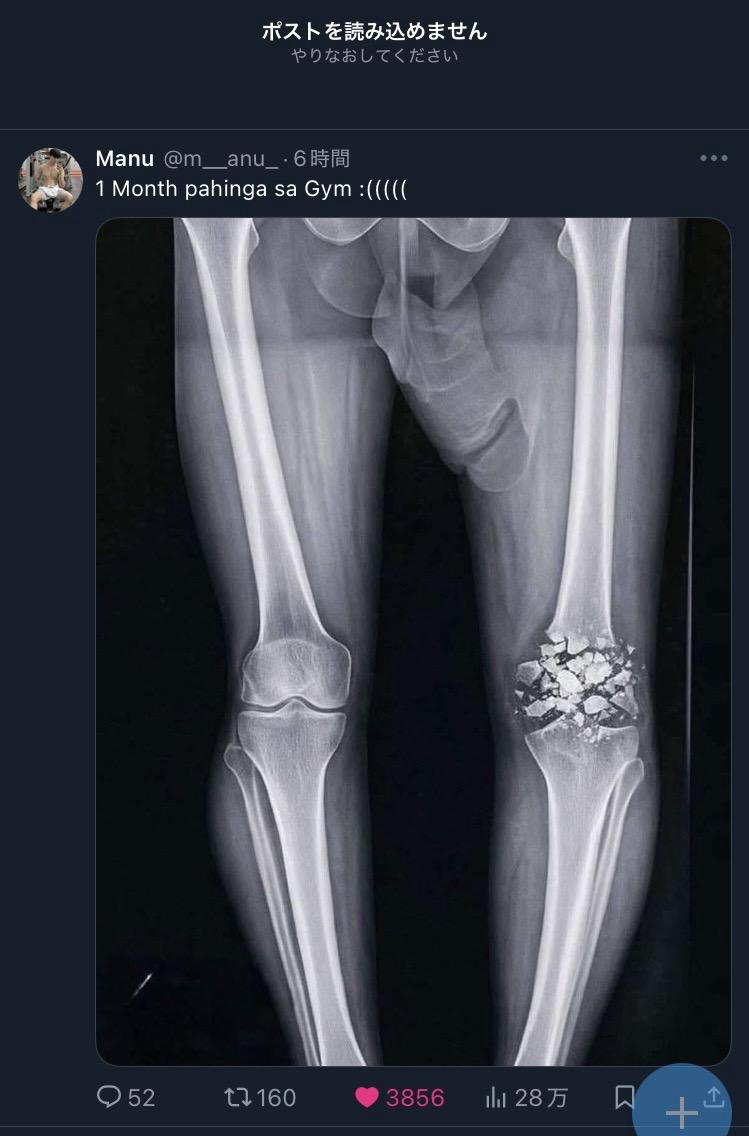

Xが止まってタイムライン更新できないんだけど

そのせいでアプリ開いたら常にこのチンポ見せつけられて困る

よく見たら全然笑えないレントゲンだった

>よく見たら全然笑えないレントゲンだった

よく見なくてもさすがに膝の方が先に目につくだろ!?

1ヶ月でどうにかなるようには見えない

チンポが先に目に入るか砕けた骨が先に目に入るかどうかでホモノンケ診断ができる画像

不健全な「」の9割はX-RAYチンポに視線を取られて粉砕骨折に気が付かない

こんな綺麗に粉々の状態で映るもんなのか…?

こんな砕け方すんのか

キレイに映りすぎでこんなこと本当にあるのかと思ってしまった

ヒビとかバキンと割れるとかじゃなくこんな粉々になるって何したんだ…

コラ?

破片全部取り除いて骨の代わり入れないとダメだな…

ここまで粉みじんになることってあるのか…

骨がこんな風に綺麗に砕けるわけないだろう

レントゲンじゃなくてCGイラストだよ

粉砕骨折を文字通りのイメージするとこういう感じになりそう

バーベル落としたとかかな?

ここまでなるやつは肉もえらいことになってそうだが…

>1ヶ月でどうにかなるようには見えない

1か月どころかもう一生治らねえ程度じゃねえかこれ?

皿が粉々だ

動かすだけで激痛だろかわうそ…

砕けてもこんな綺麗には写らないんだろうな

見た目どんな感じになってんだろこの膝

治るのこれ?

そもそもAIだからこの状態のやつはいない

骨は内部に結合組織を持ち意外に柔軟なのでこんな硬いもののような割れ方はしないし折れ方も形状や靱帯の付き方受傷機転からくる特徴が必ずある

なのでそれらすべて無視してる画像はどうみてもフェイクというかジョーク